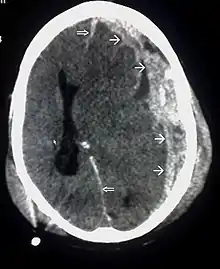

| CT scan showing cerebral contusions, hemorrhage within the hemispheres, and subdural hematoma. There is also displaced skull fracture of left transverse parietal and temporal bones.[2] | |

Hematomas, also focal lesions, are collections of blood in or around the brain that can result from hemorrhage.[11] Intracerebral hemorrhage, with bleeding in the brain tissue itself, is an intra-axial lesion. Extra-axial lesions include epidural hematoma, subdural hematoma, subarachnoid hemorrhage, and intraventricular hemorrhage.[38] Epidural hematoma involves bleeding into the area between the skull and the dura mater, the outermost of the three membranes surrounding the brain.[11] In subdural hematoma, bleeding occurs between the dura and the arachnoid mater.[23] Subarachnoid hemorrhage involves bleeding into the space between the arachnoid membrane and the pia mater.[23] Intraventricular hemorrhage occurs when there is bleeding in the ventricles.[38]